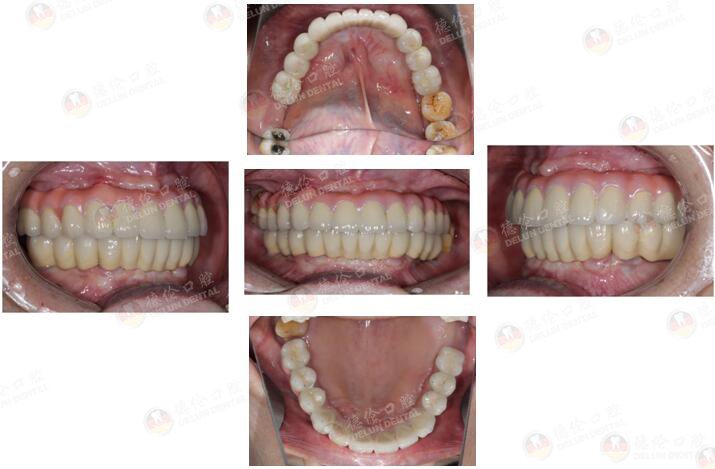

许女士 65岁

牙齿症状:全口多牙缺失十余年。

10余年前因牙周炎致全口多牙拔除,之后利用活动假牙修复,现在出现活动假牙固位差、牙龈游走性压痛等情况,希望做种植牙修复。

治疗方式:倾斜植体避开左侧上颌窦、整体支架修复、数字化3D导板种植